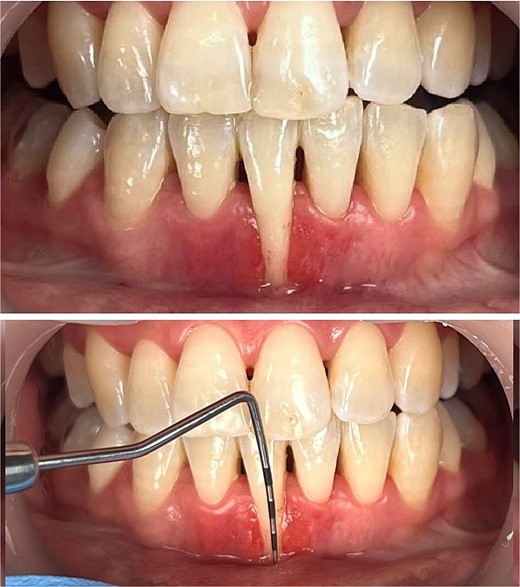

A 28-year-old medically fit female patient presented at the dental care center with severe isolated gingival recession on the lower right central incisor (tooth #41). The patient was a nonsmoker with good oral hygiene and had a history of 5-year orthodontic treatment.

The intraoral examination revealed a thin periodontal phenotype with a low full-mouth plaque score. Although there was no excessive tooth mobility, findings included narrow papillae, a shallow vestibule, a probing pocket depth of less than 3 mm, and a recession at the mandibular right central incisor, measuring 8 mm in depth and 4 mm in width. Additionally, no attached or keratinized gingival tissues were identified apical to the defect (Fig. 1).